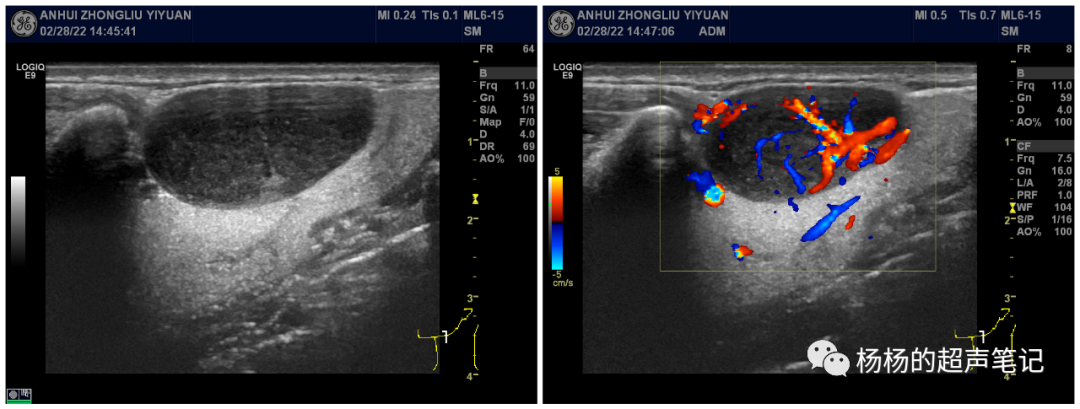

彩色图像的显示通常是先扫一帧灰阶图像,然后再扫一帧彩色多普勒的图像,彩色图像得到后再根据判断哪里是组织,哪里是血流,非血流位置就不显示彩色,再将两幅图像融合叠加在一起就得到最后的彩色图像。

彩色图像相较于灰阶图像帧频会明显下降。下图灰阶图像帧频数64帧频,彩色图像帧频数只有8帧。